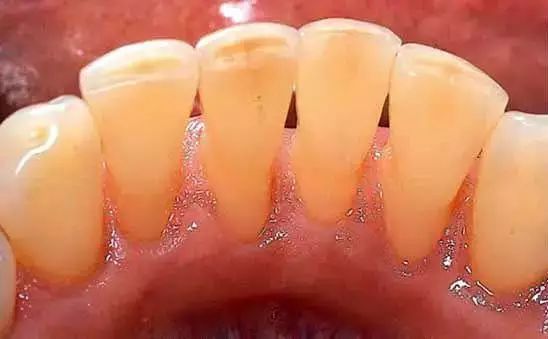

当支持牙根的牙周组织,因为平时口腔卫生差发炎、菌斑堆积时,牙齿就已经潜藏了松动的隐患,等到牙周组织流失殆尽,用不了多久,牙齿就会出现松动。所以,要及早进行牙周治疗。

1. 消除刺激物,缓解炎症。通过洗牙、龈下刮治,清除牙龈上下的牙石、牙菌斑等刺激物,消除牙龈炎症。严重一点的,需要多次复诊治疗,再严重的,可能就需要手术治疗了。